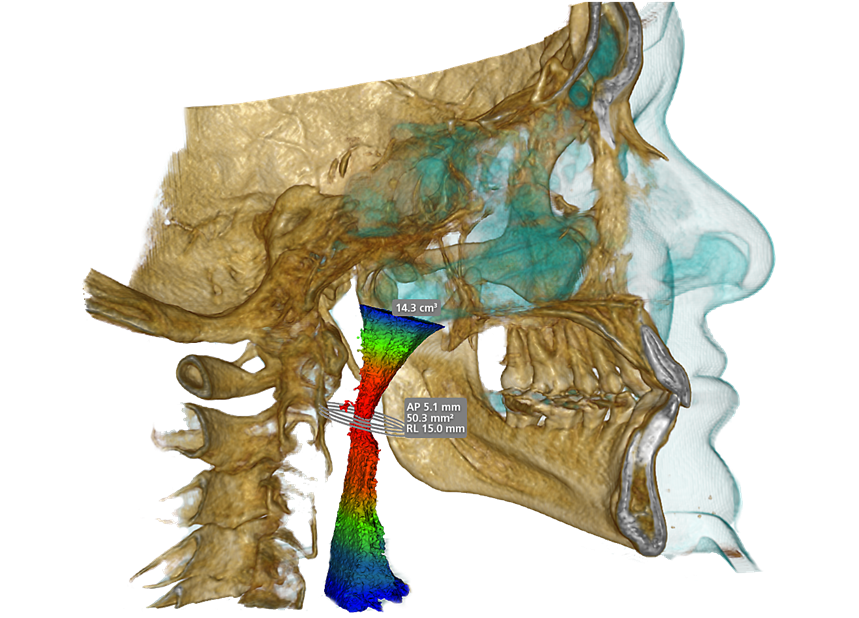

Airway Analysis